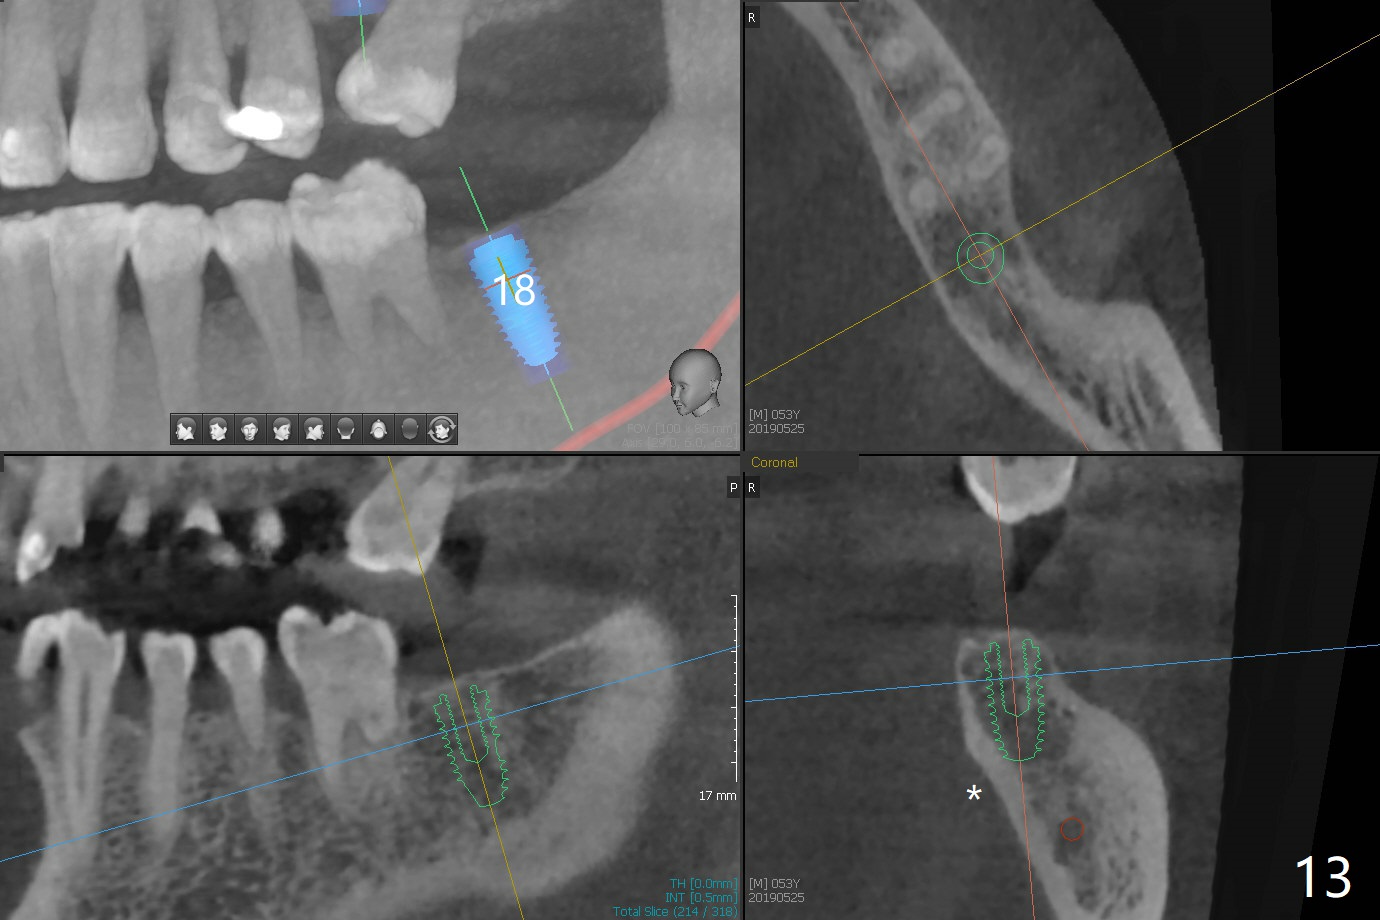

Crown/Implant Ratio

A 53-year-old man has signs of bruxism (Fig.1 diastema *) and root fracture or RCT failure at #4 (Fig.4 (large PARL *)). The RCT failure is related to overload of the affected tooth, which is in turn partially due to infraocclusion of the neighboring implant crown (Fig.1 arrows (implant positioning not ideal)) and partially to due to partial edentulism (Fig.2 missing teeth #14 and 18). For long term, limited ortho will be performed to upright and distalize the tooth #15 (Fig.3 arrow), followed by implants at #14 and 18. For now, the tooth #4 will be extracted (Fig.5), followed by osteotomy in the distal slope of the socket with guide (Fig.6 to get good trajectory). To place a bone-level implant (Fig.7 green), an abutment (blue) with long cuff (pink) is to be used. With poor implant/crown (white) ratio, stress occurs at the junction of the implant/abutment (red arrow), resulting in easy abutment screw loosening. In contrast, stress may be applied to directly to a tissue-level implant (Fig.8 arrow) with less likelihood of abutment screw loosening. The implant/crown ratio improves by approximately 5.5 mm. The roots of the teeth #15 and 16 are so close to each other that interference may occur when the tooth #15 is being uprighted (Fig.9). The empty socket of the tooth #4 is wide buccopalatal (Fig.10); the buccal plate is resorbed coronally (Fig.10 <) so that a 4.5 or 5 mm diameter implant should be placed palatal (Fig.11). Use sticky bone to repair the buccal plate defect and PRF membrane or plug for sinus lift. Following #15 uprighting and distalization, a 5x10 mm implant will be placed at #14; the ridge is triangular (Fig.12 <) so that bone trimmer is needed. A 10 mm long implant will be placed at #18 (Fig.14) to avoid perforating to the submandibular fossa (Fig.13 *).